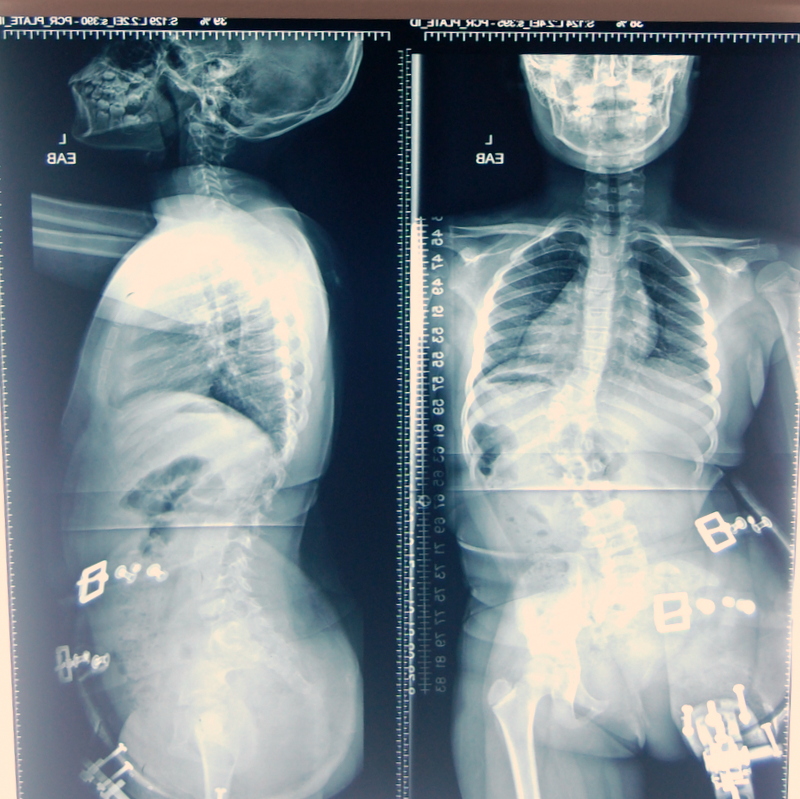

Irene is now 8 years old, she and her mom have been to the OTC many times over the years as we provide her with an artificial leg. She is a smart girl and her mother values good education so she has worked hard for Irene and her little sister and brother to attend a good school. Recently we asked her to take Irene to a spinal specialist as her back had a bad curve. After examination she was informed that Irene needed surgery to correct the scoliosis. It is important that this is done, if not she will have a lot of problems later in life.

The cost of the surgery is 44,000 (forty-four thousand Ghana Cedis) which is at the moment €11,000 or $11,600. We are working with the hospital to see if they can give us some reduction but even with that for the average Ghanaian family the cost is prohibitive. We would like very much to help Irene’s mom as she tries to have fund raisers to get the money needed so the surgery can be done as soon as possible. I would like very much if we at OTC can also help this child get the surgical care she needs.